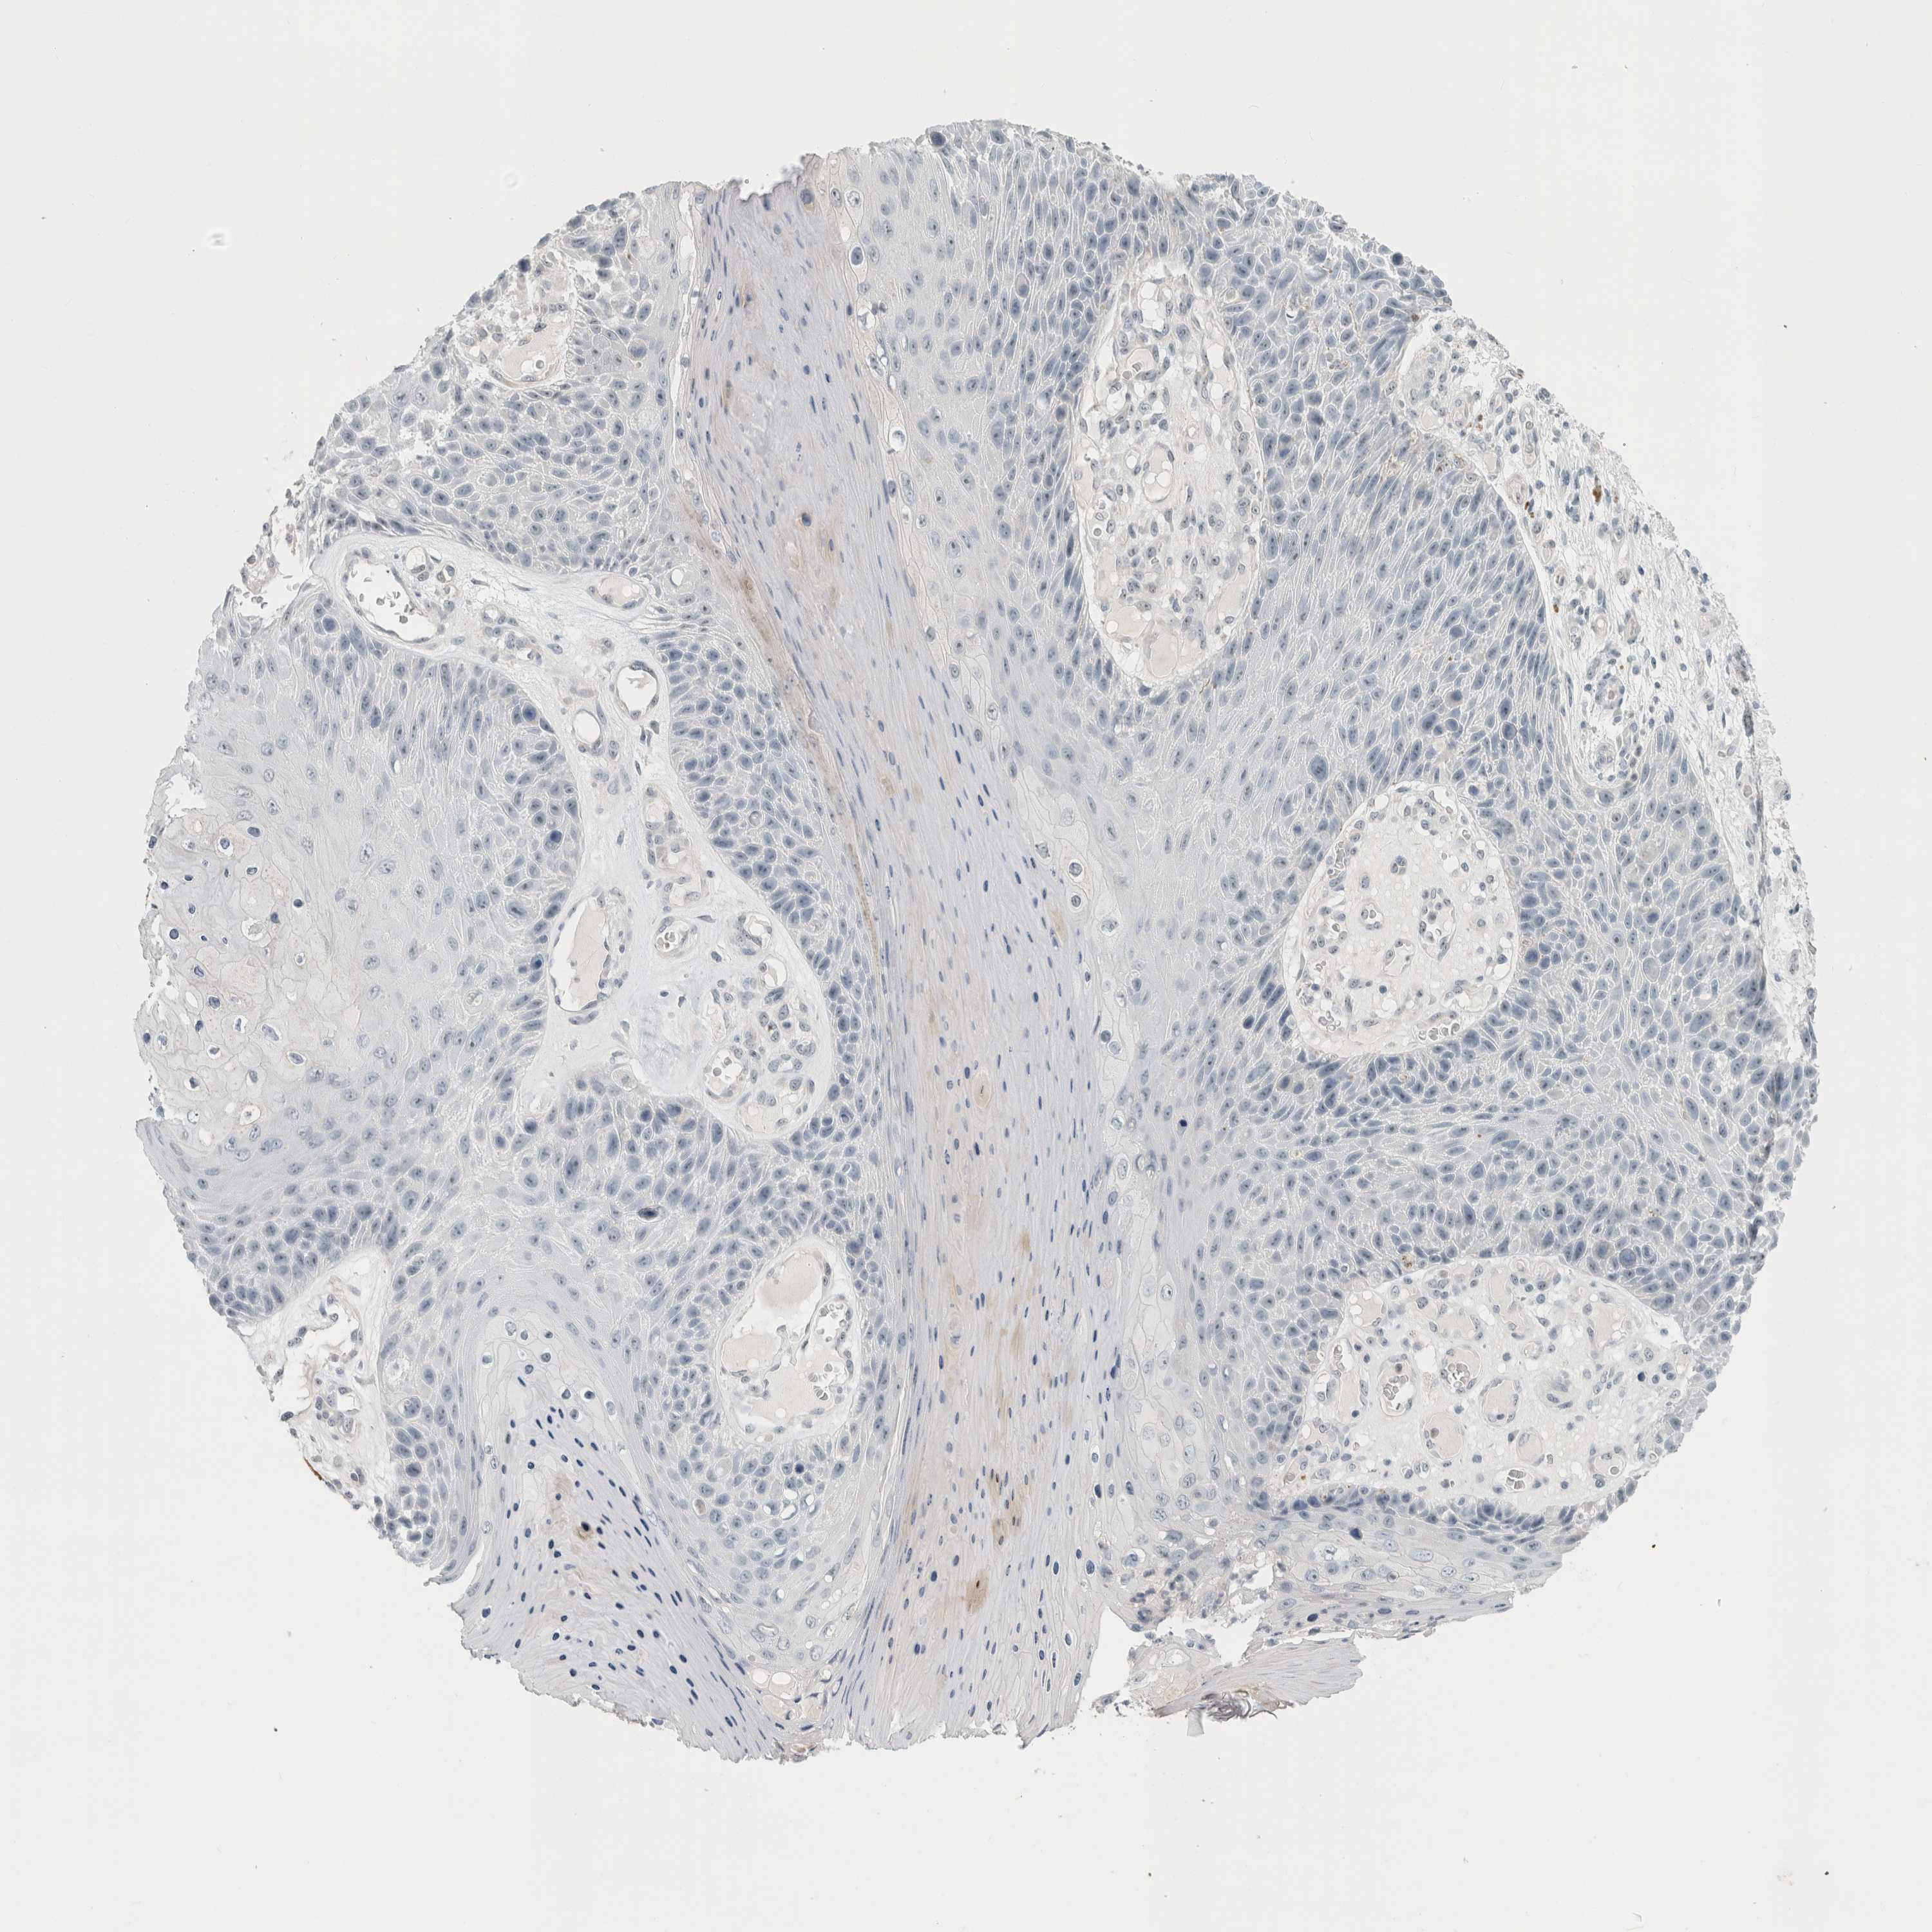

SKIN CANCER - Protein expressioni

A mouse-over function shows sample information and annotation data. Click on an image to view it in a full screen mode. Samples can be filtered based on level of antibody staining by selecting one or several of the following categories: high, medium, low and not detected. The assay and annotation is described here.

Antibody stainingi

Antibody staining in the annotated cell types in the current human tissue is reported as not detected, low, medium, or high, based on conventional immunohistochemistry profiling in selected tissues. This score is based on the combination of the staining intensity and fraction of stained cells.

Each image is clickable and will lead to virtual microscopy that enables deeper exploration of all samples and also displays staining intensity scores, fraction scores and subcellular localization as well as patient and tissue information for each sample.

Antibody HPA011284

Squamous cell carcinoma, NOS